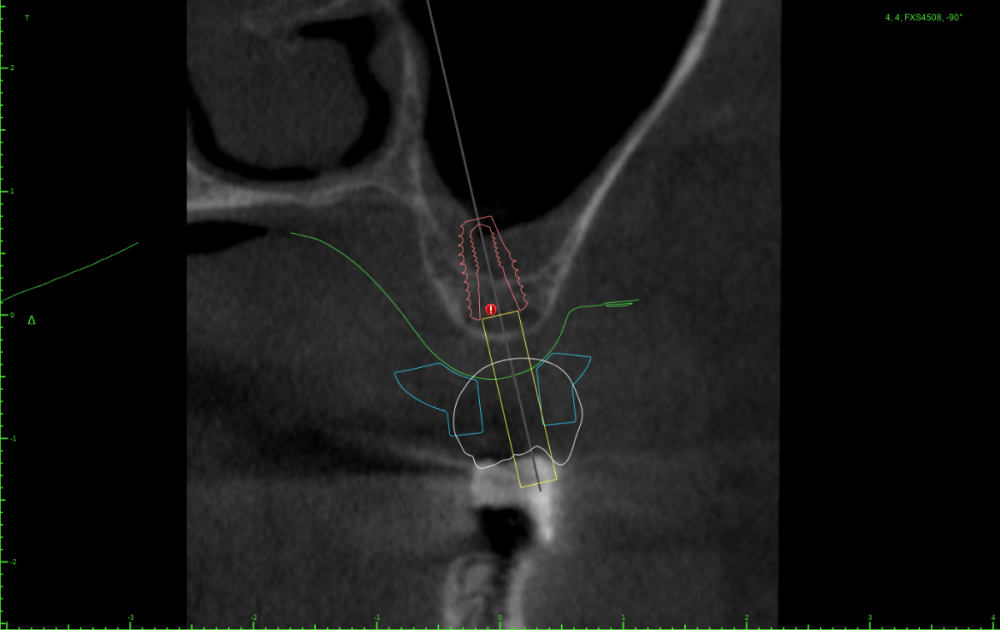

АнтонТЛТ Опубликовано 25 июля, 2023 Поделиться Опубликовано 25 июля, 2023 Значит пора выложить скрины проекта шаблона) посмотреть что там с параллельностью, если там всё параллельно, тогда искать причину почему имплантаты завалены Ссылка на комментарий

Женька Опубликовано 25 июля, 2023 Автор Поделиться Опубликовано 25 июля, 2023 23 часа назад, Женька сказал: Но буду честен, можно было чутка 1.4 наклонить и сооснопоставить. я же уже говорил об этом. Вот если бы параллелил по 1.6 . Как по мне так себе позиция Поэтому выбрана такая И соответственно если бы параллелил по 1.4 Ссылка на комментарий

АнтонТЛТ Опубликовано 25 июля, 2023 Поделиться Опубликовано 25 июля, 2023 А сагиттальный срез? Ссылка на комментарий

АнтонТЛТ Опубликовано 25 июля, 2023 Поделиться Опубликовано 25 июля, 2023 По фото выглядит так как будто установлены так Ссылка на комментарий

Женька Опубликовано 26 июля, 2023 Автор Поделиться Опубликовано 26 июля, 2023 (изменено) @АнтонТЛТ , не, не делали. Через полгодика сделаю, как раз пластика с другой стороны (сетка, которую выкладывал) должна созреть.) Возможно из-за синуса ось сместилась ну и были определённые проблемы привязки КТ и скана. Зубы есть, но программа не хотела даже по точкам сопоставлять. Пришлось в ручную. саггиталь не могу выстроить как не кручу, чтобы оба болта попали. Изменено 26 июля, 2023 пользователем Женька Ссылка на комментарий